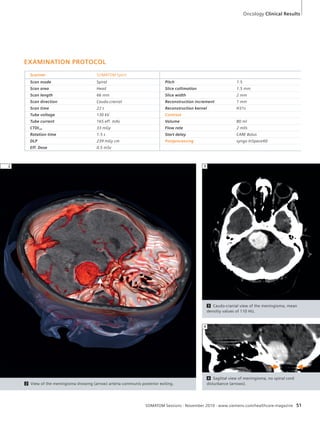

50 SOMATOM Spirit: Follow-Up Exami-nation

of Cerebral Meningioma

Neurology

to be treated as medical facilities stagger